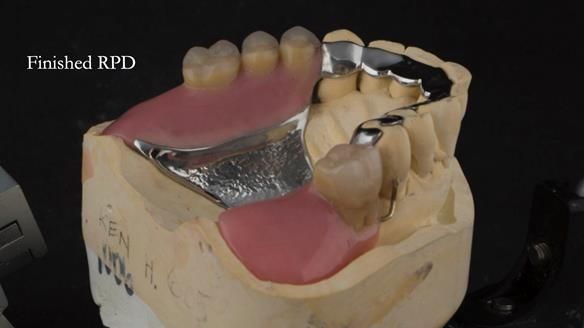

A metal-based upper RPD was made,

with metal backings incorporated to future-proof the design

should further teeth fail.

The way Rowan lengthened the teeth — particularly in the upper RPD — to match the existing gingival recession on the remaining teeth was superb. The dentures sit naturally within the context of the rest of the mouth.